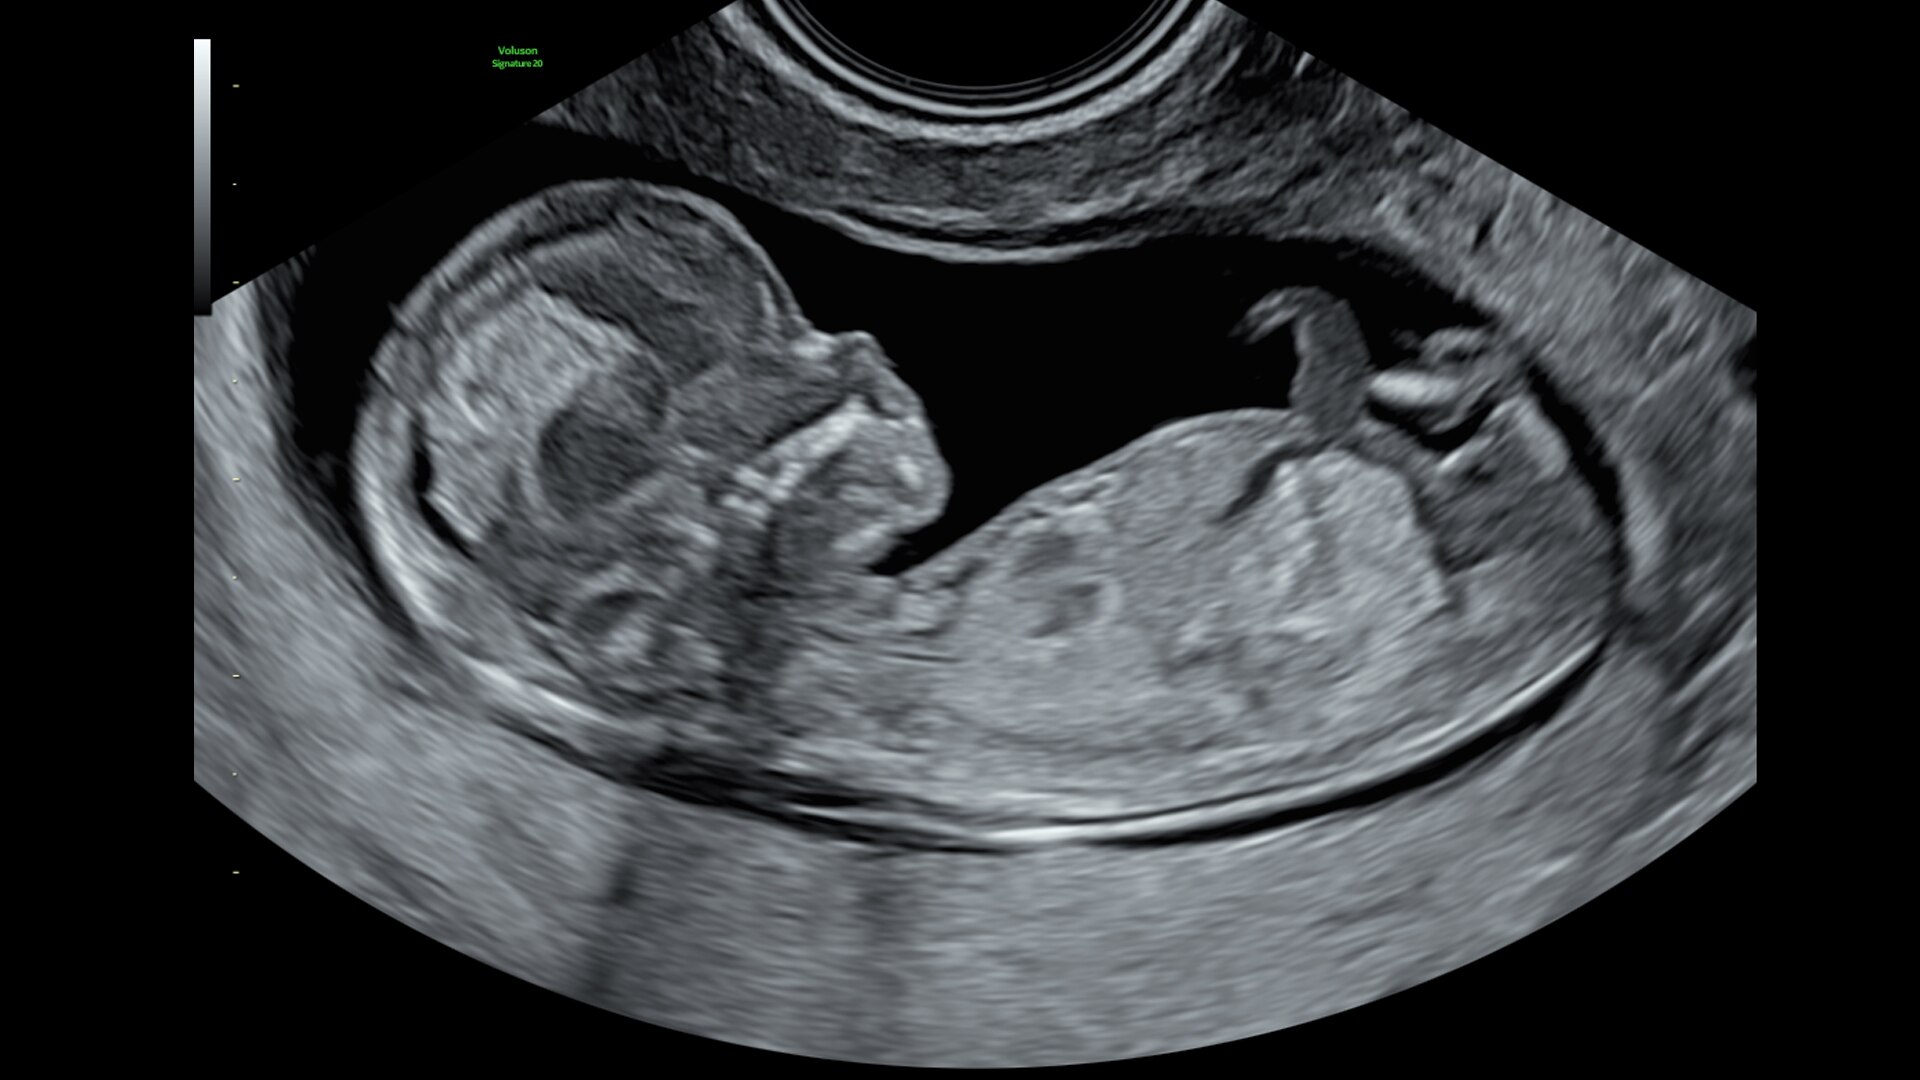

Voluson Signature20

The Voluson Signature 20 is a top performer. Powered by a progressive, highly flexible system architecture and coupled with Voluson’s advanced transducer technology migrated from our premium Expert series platform, take a big leap in image quality. With a new level of depth and clarity, accelerate your diagnostic capabilities so you can always deliver your most confident care.

Advanced beamforming capabilities work in harmony with expert-level probes to deliver faster processing speeds and frame rates for enhanced detail and contrast resolution, greater color quality and sensitivity, and exceptional 3D/4D.